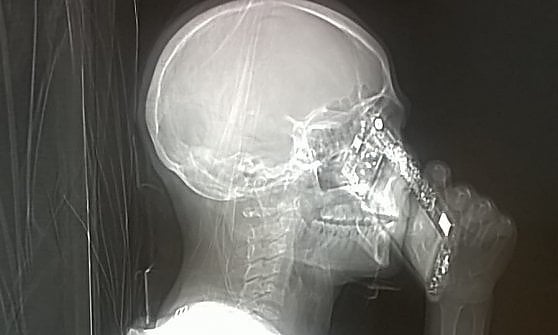

Incredibile quello che i medici hanno visto al momento che hanno ritirato la tac. Un paziente ha una terribile emicrania e approda al pronto soccorso del Cardarelli, il più grande ospedale del Mezzogiorno. La donna arriva in Neuro-Radiologia accompagnata dai familiari e i medici le prescrivono una tac urgente. In una manciata di minuti i tecnici fanno entrare la paziente nell’area radiologica e la sistemano davanti all’apparecchiatura per eseguire la tac cerebrale. Dalla consolle esterna intanto il personale controlla con una prima schermata che la posizione del corpo sia giusta per acquisire le immagini definitive. Ed ecco la sorpresa. Davanti agli occhi esterefatti degli specialisti compare la sagoma scheletrica della signora che tiene un cellulare all’orecchio. Pronta a rispondere a una chiamata.

La donna aveva portato il telefonino con sè, cosa vietata dal regolamento. Ai radiologi non è rimasto altro da fare che sospendere l’esame, mentre la paziente mortificata si è giustificata: “Mi dispiace, l’ho dimenticato”. La tac è stata poi effettuata regolarmente e dal referto non è risultata alcuna patologia. L’immagine scattata dall’ospedale probabilmente diventerà virale, simbolo di un’epoca dominata dagli smartphone.